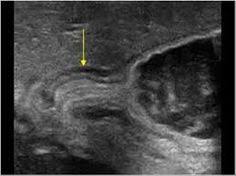

Idea Of Echographie de la thyroide PDF